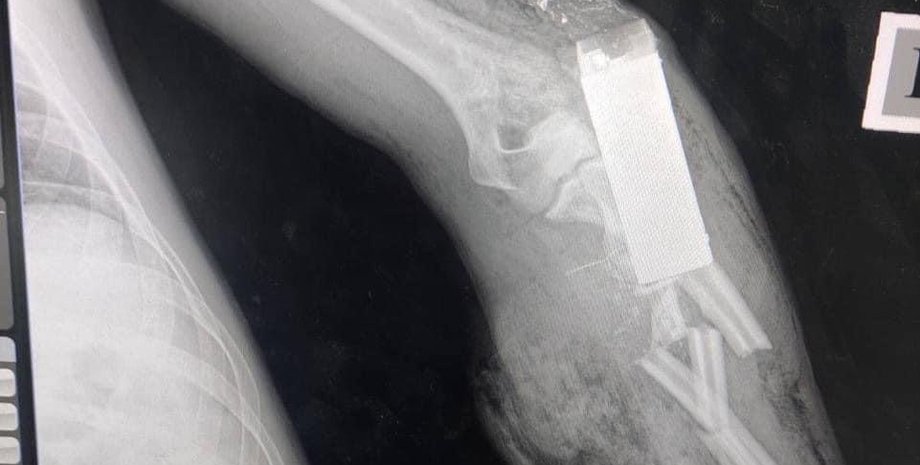

Из тела украинского защитника военные врачи достали боевой элемент гранаты | Фото: Медичне командування ЗСУ

По словам медиков, элемент гранаты попал военнослужащему в руку.

"То, что вы видите на фото — боевой элемент гранаты ВОГ-17, который попал прямо в руку украинского защитника. К счастью, наши военные врачи достали его из руки раненого, спасая ему не только жизнь, но и конечность", — говорится в сообщении.